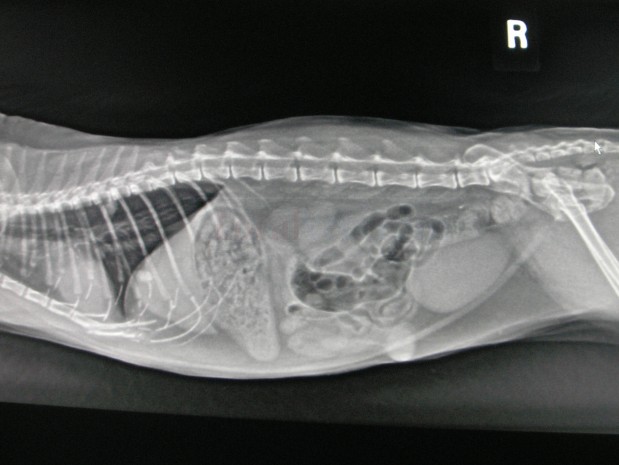

Radiology (X-ray) is a non-invasive diagnostic tool used to assist in the diagnosis of many concerning conditions and traumas.

• OFA Hips and Elbows